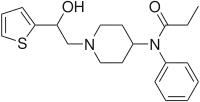

Anilidopiperidines

- 3-Allylfentanyl

- 3-Methylfentanyl

- 3-Methylthiofentanyl

- 4-Phenylfentanyl

- Alfentanil

- α-Methylacetylfentanyl

- α-Methylfentanyl

- α-Methylthiofentanyl

- Benzylfentanyl

- β-hydroxyfentanyl

- β-hydroxythiofentanyl

- β-Methylfentanyl

- Brifentanil

- Butyrfentanyl

- Carfentanil

- Fentanyl

- Lofentanil

- N-Methylcarfentanil

- Mirfentanil

- Ocfentanil

- Ohmefentanyl

- Parafluorofentanyl

- Phenaridine

- R-30490

- Remifentanil

- Sufentanil

- Thenylfentanyl

- Thiofentanyl

- Trefentanil

Structures